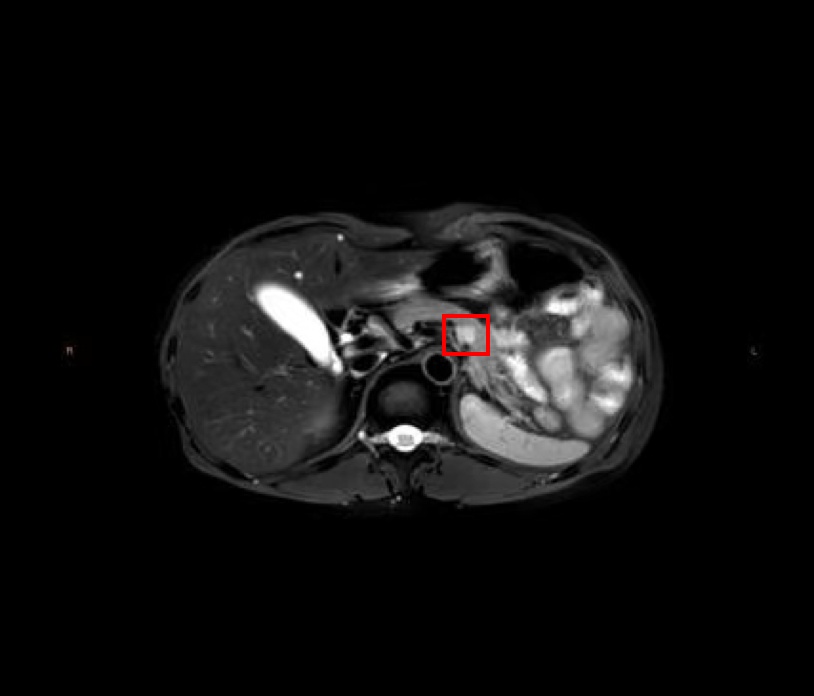

治疗前、疫苗前/后 影像图